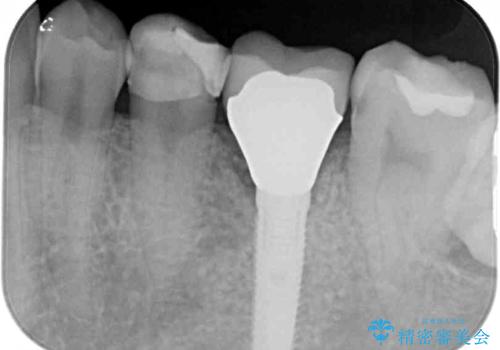

- 奥歯がしみて痛いとのことで来院された患者様です。

既に複数箇所の修復が行われていたため、オールセラミッククラウンにて補綴をすることとしました。

以前装着した修復物が不適であり、歯肉が腫れていましたが、仮歯を装着したことで腫れは解消されました。